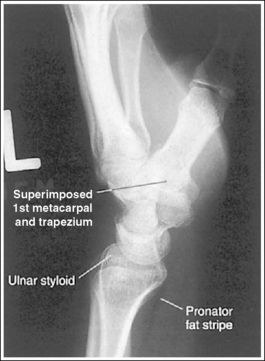

See Figure 4-36 and Box 4-13.

Contrast and density are adequate to demonstrate the pronator fat stripe and surrounding posterior wrist soft tissue.

• The pronator fat stripe is one of the soft tissue structures that should be demonstrated on all lateral wrist projections (Figure 4-37). It is located parallel to the anterior (volar) surface of the distal radius, is normally convex, and lies within 0.25 inch (0.6 cm) of the radial cortex. Bowing or obliteration of this fat stripe may be the only indication of a subtle radial fracture.

The wrist is in a lateral projection. The anterior aspect of the distal scaphoid and pisiform are aligned, and the radius and ulna are superimposed.

• A lateral projection of the wrist is accomplished by flexing the elbow 90 degrees and abducting the humerus until it is parallel with the IR, placing the entire arm on the same horizontal plane. Rotate the wrist into a lateral projection with its ulnar (medial) aspect against the IR (Figure 4-38). To ensure a true lateral projection, place the palmar aspect of your thumb and forefinger against the anterior and posterior aspects, respectively, of the patient's wrist joint, as shown in Figure 4-39. Adjust wrist rotation until your thumb and finger are aligned perpendicular to the IR.

• Detecting wrist rotation. The relationship between the pisiform and distal aspect of the scaphoid can best be used to discern whether a lateral wrist projection has been obtained. On a lateral projection, these two carpals should be superimposed, with their anterior aspects aligned. When the wrist is rotated, the anteroposterior relationship between the distal scaphoid and pisiform changes, and the pronator fat stripe is obscured. If the anterior aspect of the distal scaphoid is positioned posterior to the anterior aspect of the pisiform, the patient's wrist was externally rotated (see Image 45). If the anterior aspect of the distal scaphoid is positioned anterior to the anterior aspect of the pisiform, the patient's wrist was internally rotated (see Images 46 and 47). A second method of determining how to reposition a rotated lateral wrist projection uses the radius and ulna. The ulna is positioned anterior to the radius when the wrist was externally rotated and the ulna is positioned posterior to the radius when the wrist was internally rotated. Because the exact amount of superimposition of the radius and ulna depends on the position of the humerus, and their poor positioning is not as sensitive, you should always view the pisiform and distal scaphoid relationship when determining whether the wrist is in a lateral projection.

• Mediolateral wrist projection. Routinely, the lateral wrist projection is taken with the ulnar side of the wrist against the IR. If, instead, the radial side of the wrist was placed against the IR (mediolateral projection), the ulna and pisiform are visualized anterior to the radius and scaphoid, respectively, and the ulnar styloid is demonstrated in profile anteriorly (see Image 48).